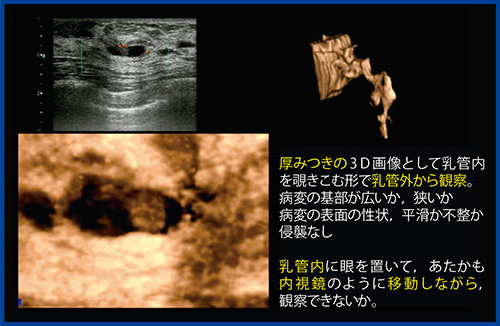

乳頭から責任乳管にカニュレーションしてヨード系造影剤を注入し,マンモグラフィを撮影する乳管造影をバーチャルで表現するために,厚みをつけた拡張乳管画像を白黒反転し,低エコーな乳管を立体的な白い構造物として再構成することで,バーチャルな3D乳管造影像が得られる。バーチャル乳管造影では非侵襲的に乳管の拡張,狭小,腫瘤などの所見が得られる。また,バーチャル乳管内視鏡では厚みつき画像で乳管内をのぞき込む形で,乳管外から病変の基部の太さや性状が観察可能であった(図2)。

図2 厚みつき画像によるバーチャル乳管造影・内視鏡像

次の段階として,乳管内に視点を置き,あたかも内視鏡のように移動しながら観察できないかと考えた。東芝メディカルシステムズが開発したアプリケーション“FlyThru”は,3Dプローブで取得したボリュームデータから透視投影像を再構成することで,管腔内を立体的に移動する画像を得ることができる。このFlyThruを乳腺領域に応用し,バーチャル乳管内視鏡として2011年5月に報告した。実際の乳管内視鏡検査は,外径0.8mmの内視鏡を乳頭から挿入し,空気で乳管を膨らませて乳管内を観察する。すでに臨床応用が進んでおり,乳管内病変については形状や色によって鑑別診断が可能と言われている。